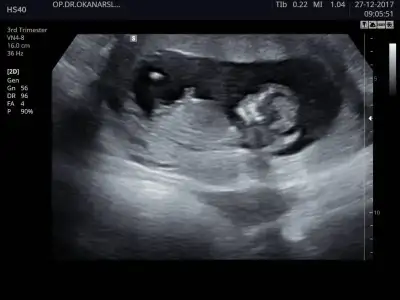

Merhaba, ultrason görüntülerinde sat'a göre 11+4 üz.

cinsiyet tahmini yapabilecek olan var mı:)